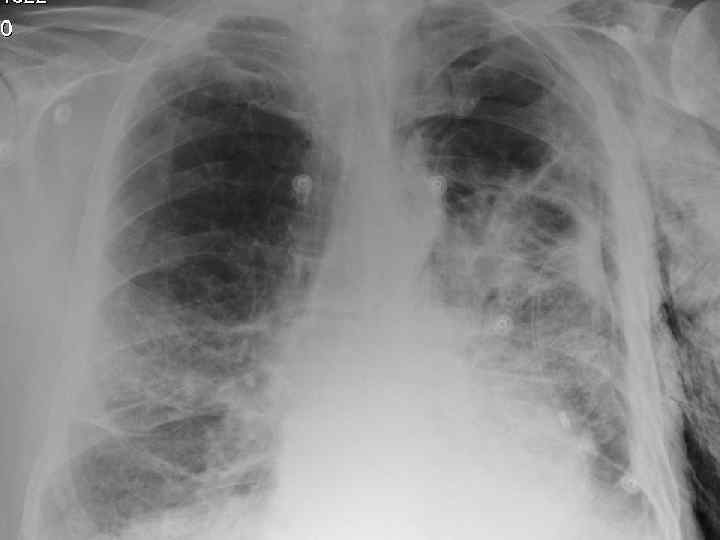

History n Mr X is a 74 year old Caucasian male n PC: Acute SOB n HPC: SOB episode began at 10 -11 am this morning gradually worsening, but suddenly became acutely worse. Noticed by neighbour. Ambulance blue lighted to AE resus

Examination n n n Anxious, gasping for breath, holding arms on trolley, Abdominal muscles used for breathing Central cyanosis Pulse 106 bmp regular HS I + II + 0 Apex beat laterally displaced Pitting right ankle oedema No sacral oedema

Respiratory R n n n L Resp rate 22 pm Trachea central Uneven lung expansion Hyperinflated upper chest Hyperresonant percussion Exp wheezing Insp crackles

Impressions n Pneumothorax n COPD/Fibrosing alveolitis n AHA n Congestive heart failure n Newly diagnosed Diabetes mellitus

Investigations. n CXR n CT n Arterial blood gases

Clinical features n Progressive breathlessness n Cyanosis n Pulmonary hypertension/cor pulmonale n Clubbing n Bilateral fine end insp. Crackles n X-ray shows ground glass appearance

Investigations n Chest X-ray n High res. CT scan n Respiratory function tests n Blood gasses n ANF, RF, ESR n Bronchoalveolar lavage n Biopsy